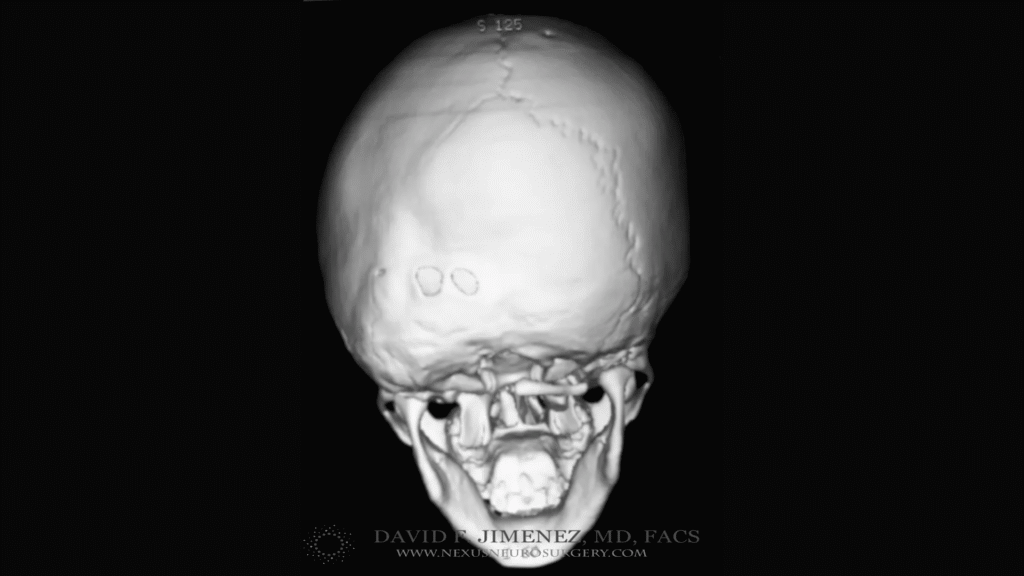

At El Paso Craniofacial Team, the primary treatment for craniosynostosis is surgery. First performed in the late 1800s, surgical approaches have continued to evolve and improve. The two main approaches are Calvarial Vault Remodel (CVR) and endoscopic-assisted surgery, with each tailored to the child’s age, the affected suture, and the severity of the condition.